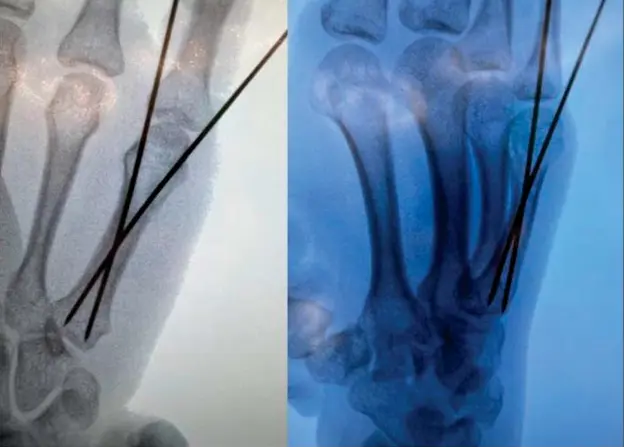

3. Percutaneous K-Wire Fixation for Metacarpal Neck Fractures

Percutaneous K-Wire Fixation (1).webp

Percutaneous K-Wire Fixation2 (1).webp

4. Percutaneous K-Wire Fixation for Adjacent Metacarpal Neck and Base Fractures